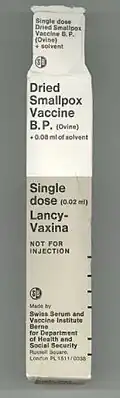

As the oldest vaccine, the smallpox vaccine has gone through several generations of medical technology. From 1796 to the 1880s, the vaccine was transmitted from one person to another through arm-to-arm vaccination. Smallpox vaccine was successfully maintained in cattle starting in the 1840s, and calf lymph vaccine became the leading smallpox vaccine in the 1880s. First-generation vaccines grown on the skin of live animals were widely distributed in the 1950s–1970s to eradicate smallpox. Second-generation vaccines were grown in chorioallantoic membrane or cell cultures for greater purity, and they were used in some areas during the smallpox eradication campaign. Third-generation vaccines are based on attenuated strains of vaccinia and saw limited use prior to the eradication of smallpox.[16]

The first-generation vaccines are manufactured by growing live vaccinia virus in the skin of live animals. Most first-generation vaccines are calf lymph vaccines that were grown on the skin of cows, but other animals were also used, including sheep.[16] The development of freeze-dried vaccine in the 1950s made it possible to preserve vaccinia virus for long periods of time without refrigeration, leading to the availability of freeze-dried vaccines such as Dryvax.[18][19]: 115

| 2022 | 35 | Lancy-Vaxina (1st)[70][71] | |